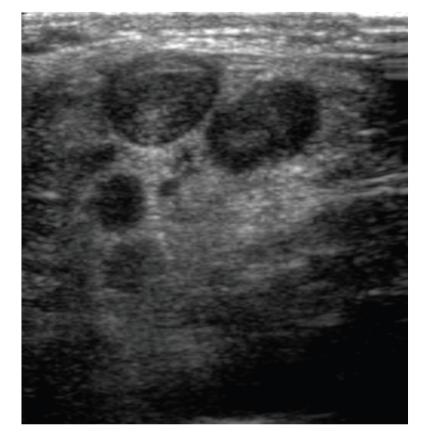

Metastatic carcinoma of unknown primary presenting as jugular venous thrombosis.

Jugular venous thrombosis is unusual and is associated with central venous catheterisation, intravenous drug abuse and head and neck sepsis. It is rarely associated with malignancy. We report a case of metastatic carcinoma of unknown primary in a forty year old female which presented with jugular venous thrombosis. The discussion includes investigation and treatment options for this condition.